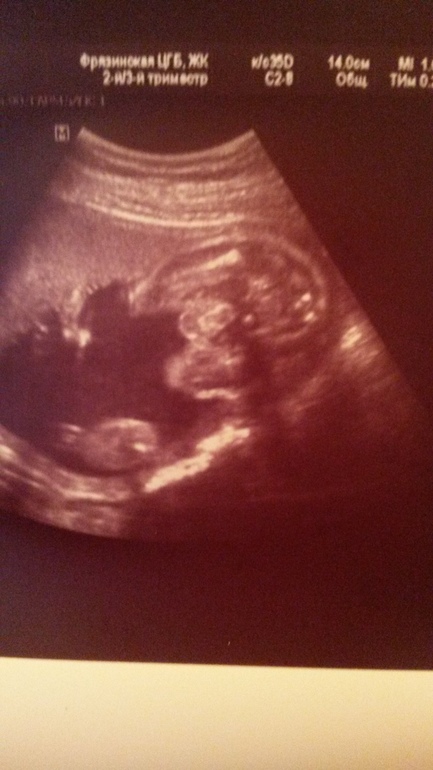

Точно мальчик! У меня так с сыном было)) А сейчас на узи отчетливо пирожок виден при таком же ракурсе))

Если это вид снизу, то пипирка очень хорошо видна - парень)

Видела я фото точь в точь, и это были мальчики

Писюн. У нас такой же снимок с сыном.

По-моему,отчетливо виден мальчуковый писюн))